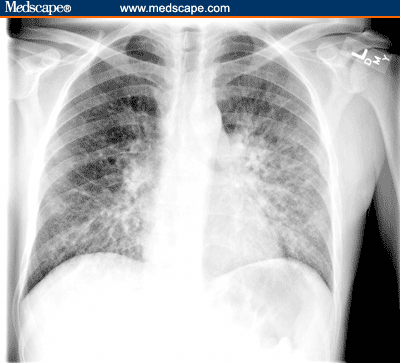

The patient returned to clinic 4 weeks later with a 1-week history of fever, dyspnea on exertion, cough, and diarrhea. The patient was febrile with a temperature of 38.3° C. There were several new cutaneous lesions and the palatal lesion had increased to 3 x 4 cm2. The plasma HIV-1 RNA level had decreased to 800 copies/mL and the CD4+ cell count increased to 320 cells/mcL. A chest radiograph and CT scan were performed (Figures 2a and 2b).

Figure 2b.

Chest CT scan of HIV-infected man with Kaposi's sarcoma.

Other laboratory abnormalities included a hematocrit of 19.8% and a platelet count of 45,000/mcL. The patient was admitted and underwent bronchoscopic examination, which revealed multiple raised vascular lesions consistent with KS throughout the tracheobronchial tree. A bone marrow biopsy revealed plasma cell dyscrasia without obvious monoclonality or hyperplasia of red cell precursors. The anemia and thrombocytopenia were poorly responsive to transfusion. Extensive work-up of the pulmonary lesions and hematologic manifestations revealed no HIV-1-related opportunistic infection or complication other than KS.